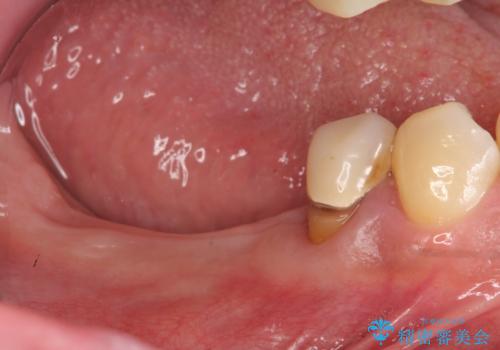

- 歯周病が進行し、根尖付近まで歯槽骨(歯を支える骨)の吸収が見られる歯の治療を希望され来院されました。

長期的な予後の見込めない奥歯の抜去を行い、骨と歯ぐきの治癒を待ち、インプラント治療を計画します。